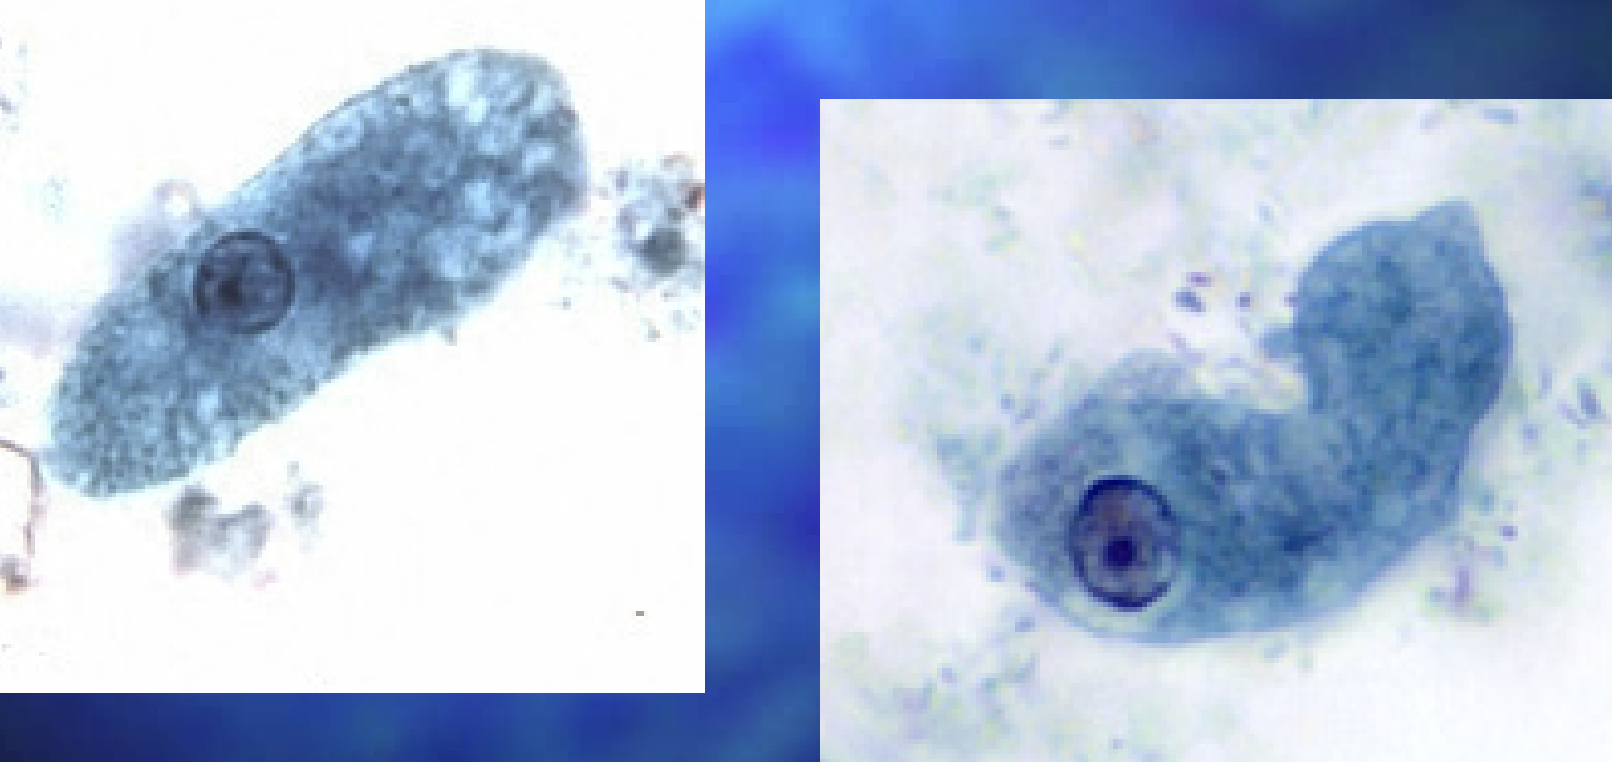

Naegleria fowleri

Naegleria fowleri

Naegleria fowleri cyst

With naegleria fowleri in CSF what is the most important treatment for the fluid

Room temp to see motility